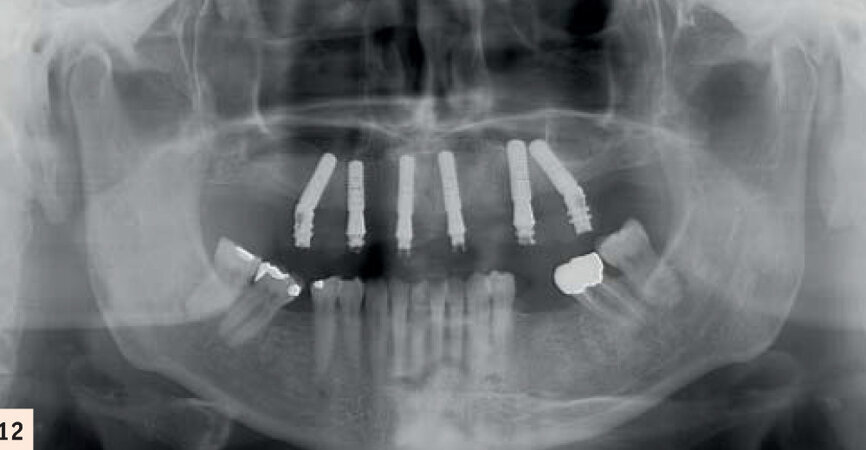

Après 2 mois d’ostéointegration (Fig. 12), commence la phase prothétique où le Hi Tech permet de finaliser un bridge céramique transvissé sur piliers multibases Straumann.L’armature est conçue et fabriqué par ordinateur par Createch (laboratoire Straumann), d’après le wax up de notre laboratoire de prothèse validé en bouche. La précision Cadcam est extrême et l’ajustage parfait (Fig 13).

Armature Cadcam Createch Straumann. Noter l’ossification autour des implants ayant soulevé la membrane sinusienne.

Radiographie après la période d’ostéoactivation.